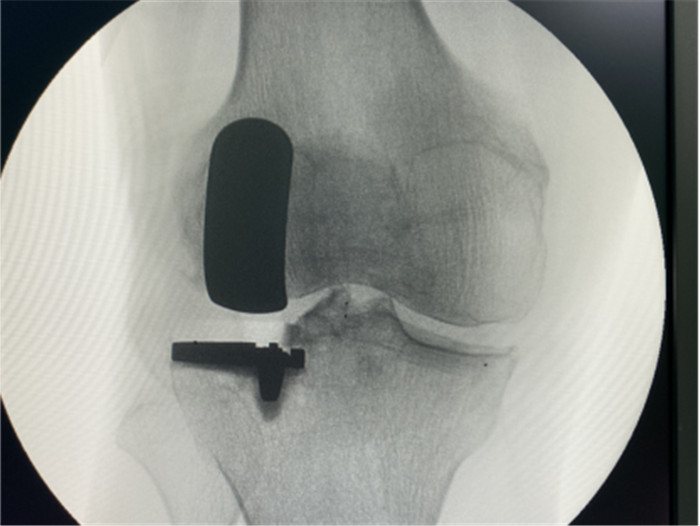

一個單髁置換手術(shù)要想達(dá)到理想的手術(shù)治療效果并不簡單,這與假體的大小、方向和松緊度密切相關(guān),其中任何一點出現(xiàn)差池,結(jié)果都會差強人意。為此,羅主任團(tuán)隊在術(shù)前和術(shù)中進(jìn)行了精確的設(shè)計和測量,制定周密手術(shù)方案,順利為病人實施手術(shù),幫助膝關(guān)節(jié)“補牙”。

接診后羅軍主任詳細(xì)檢查病人,發(fā)現(xiàn)病人疼痛癥狀主要集中在膝關(guān)節(jié)外側(cè)間室,右下肢有明顯外翻畸形。這些癥狀都是單髁置換的適應(yīng)癥。雙下肢全長攝片和右膝內(nèi)翻、外翻位攝片顯示,膝關(guān)節(jié)外側(cè)間隙消失,膝外翻畸形,果不其然印證了上述臨床表現(xiàn)。收治入院后,羅主任團(tuán)隊決定為患者實施微創(chuàng)膝關(guān)節(jié)外側(cè)單髁置換術(shù),盡全力為張大爺解除病痛的折磨。